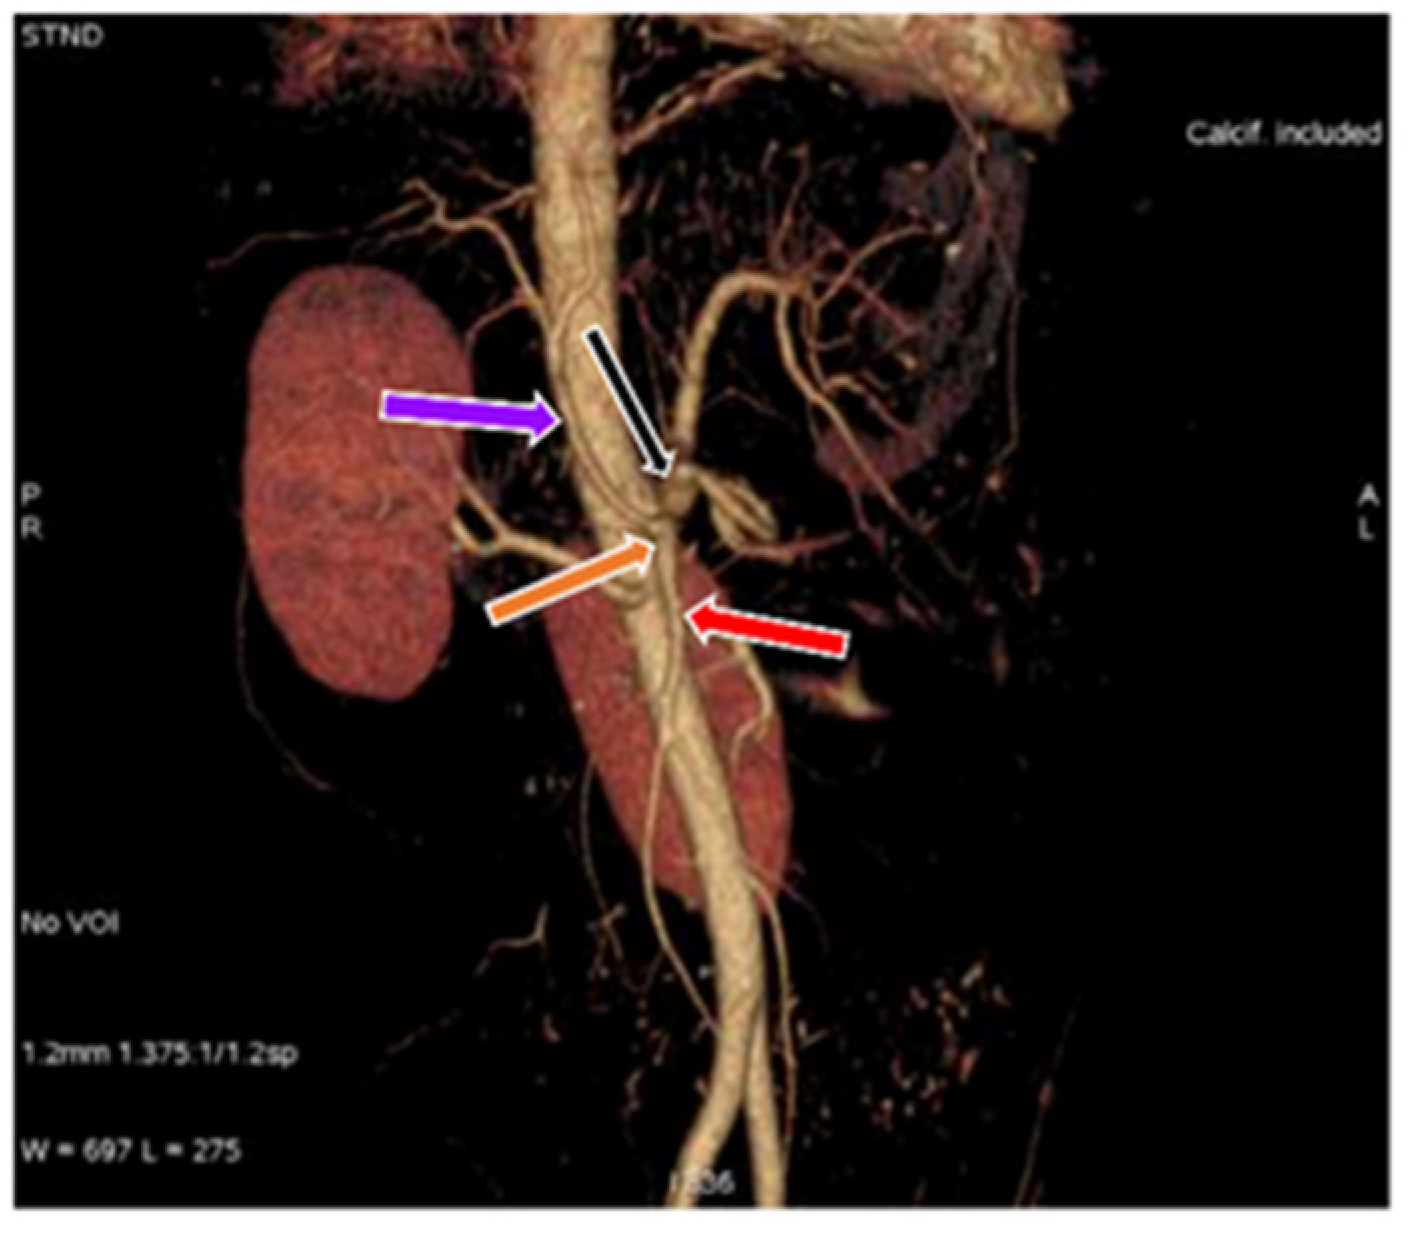

3.1. Variation in Origin and Branching Pattern of Celiac Trunk

3.2. Variation in Origin and Branching Pattern of Hepatic Artery